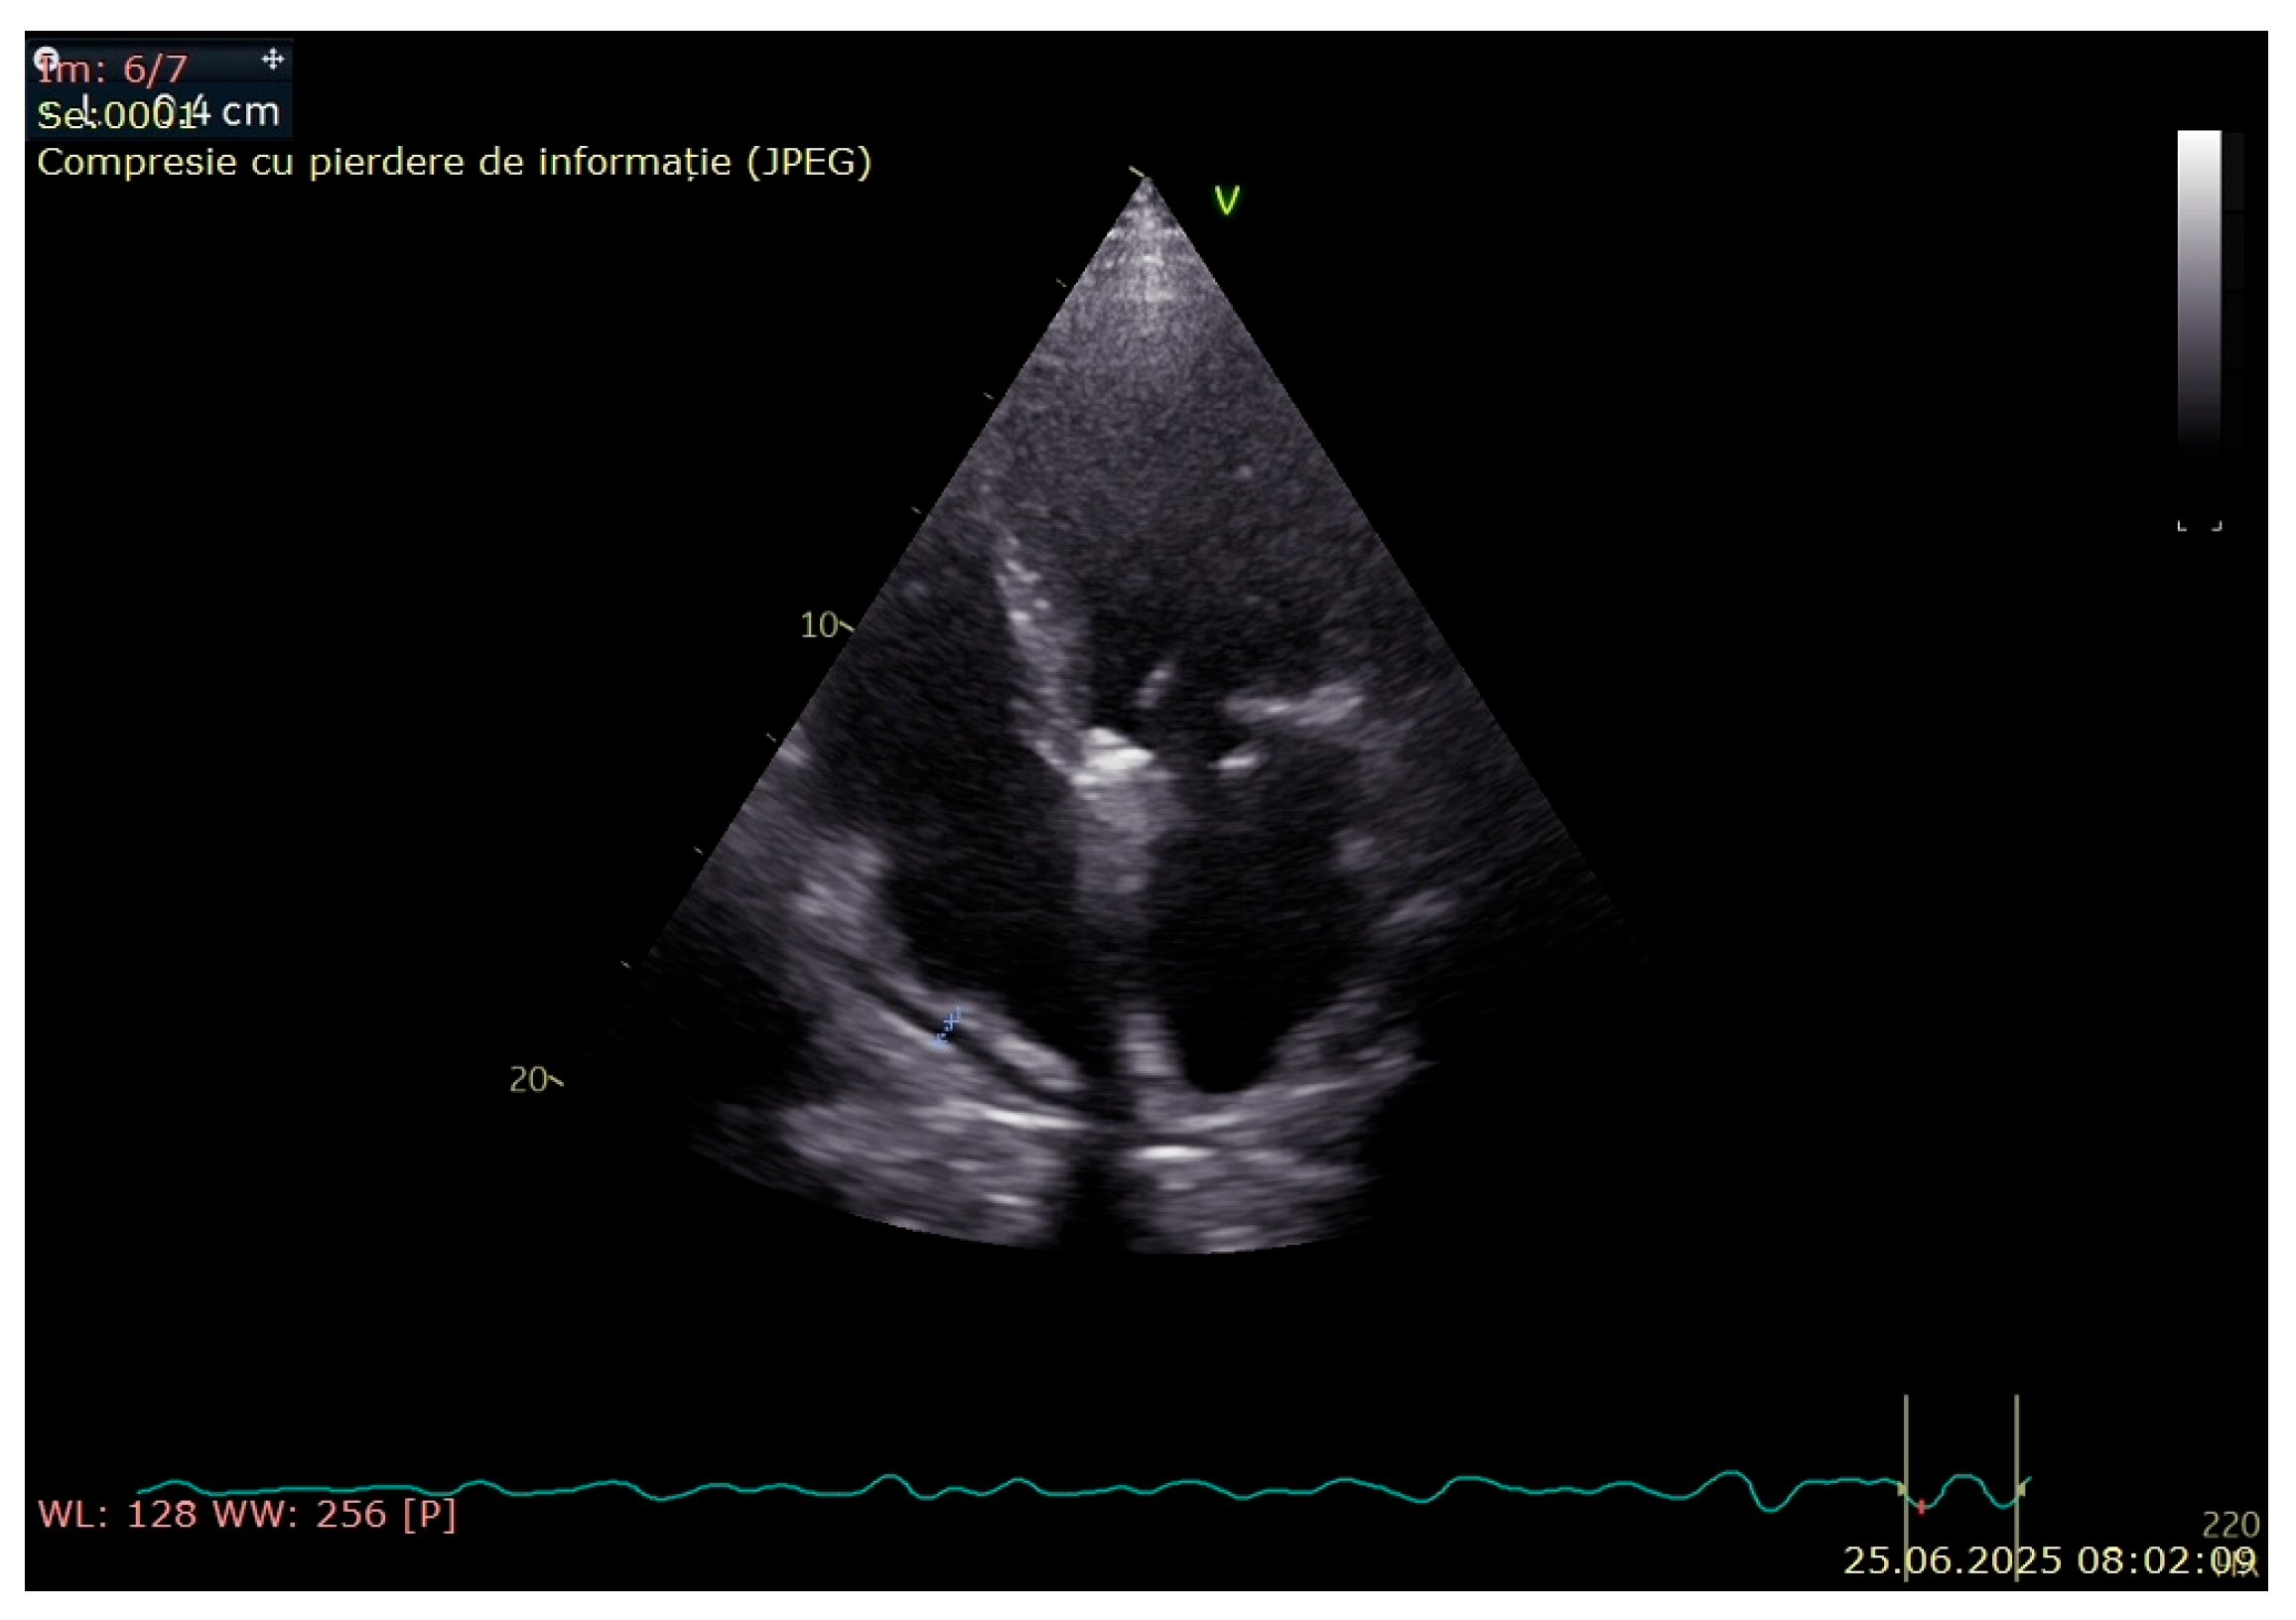

3. Case Presentation